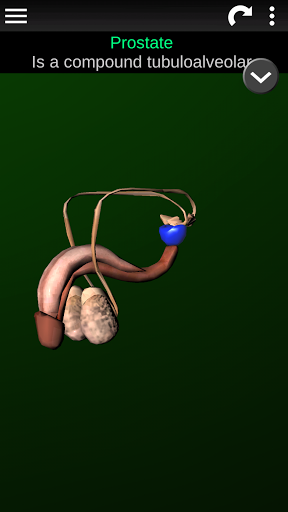

* Sistem reproduksi, yang meliputi organ reproduksi pria dan wanita.